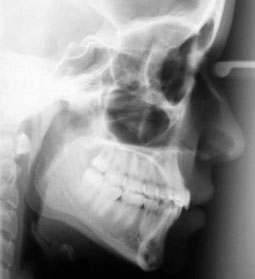

Téléradiographie de fin de traitement : position correcte des incisives (Fig. 18).